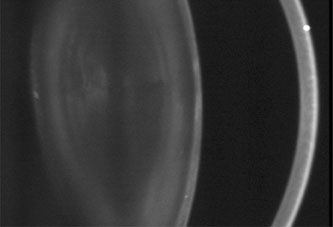

Anterior lenticonus (Figs. 8 and 9) is considered an integral part of AS. The anterior capsule thins and allows the lens to bulge into the anterior chamber, using the pupil as a mold.53 Electron microscopy of the renal glomeruli and anterior lens capsule can confirm capsular thinning and dehiscences.54,55 Anterior lenticonus is typically diagnosed in the second and third decades of life, when it causes clinically significant decreased vision,56 but it may be present in adolescence and result in spontaneous rupture of the anterior lens capsule.57 Posterior subcapsular cataract occurs quite frequently; however, many patients receive glucocorticosteroids for their renal condition, which may play an etiologic role in these cataracts. Additional ocular features described in XLAS include other corneal dystrophies, microcornea, corneal arcus, iris atrophy, posterior lenticonus, spontaneous lens rupture, spherophakia, a poor macular reflex, fluorescein angiogram hyperfluorescence, electrooculogram and ERG abnormalities, and retinal pigmentation abnormalities.58

Fig. 8. AS. The thinned lens capsule and anterior cortex protrude centrally into the anterior chamber and an additional small, central, posterior, subcapsular opacity in a 38-year-old male with AS (Scheimpflug image).

Fig. 9. AS. Oil-droplet appearance of anterior lenticonus in retroillumination. (Courtesy of Dr. N. Meadow, Manhattan Eye and Ear Hospital, New York, New York.)